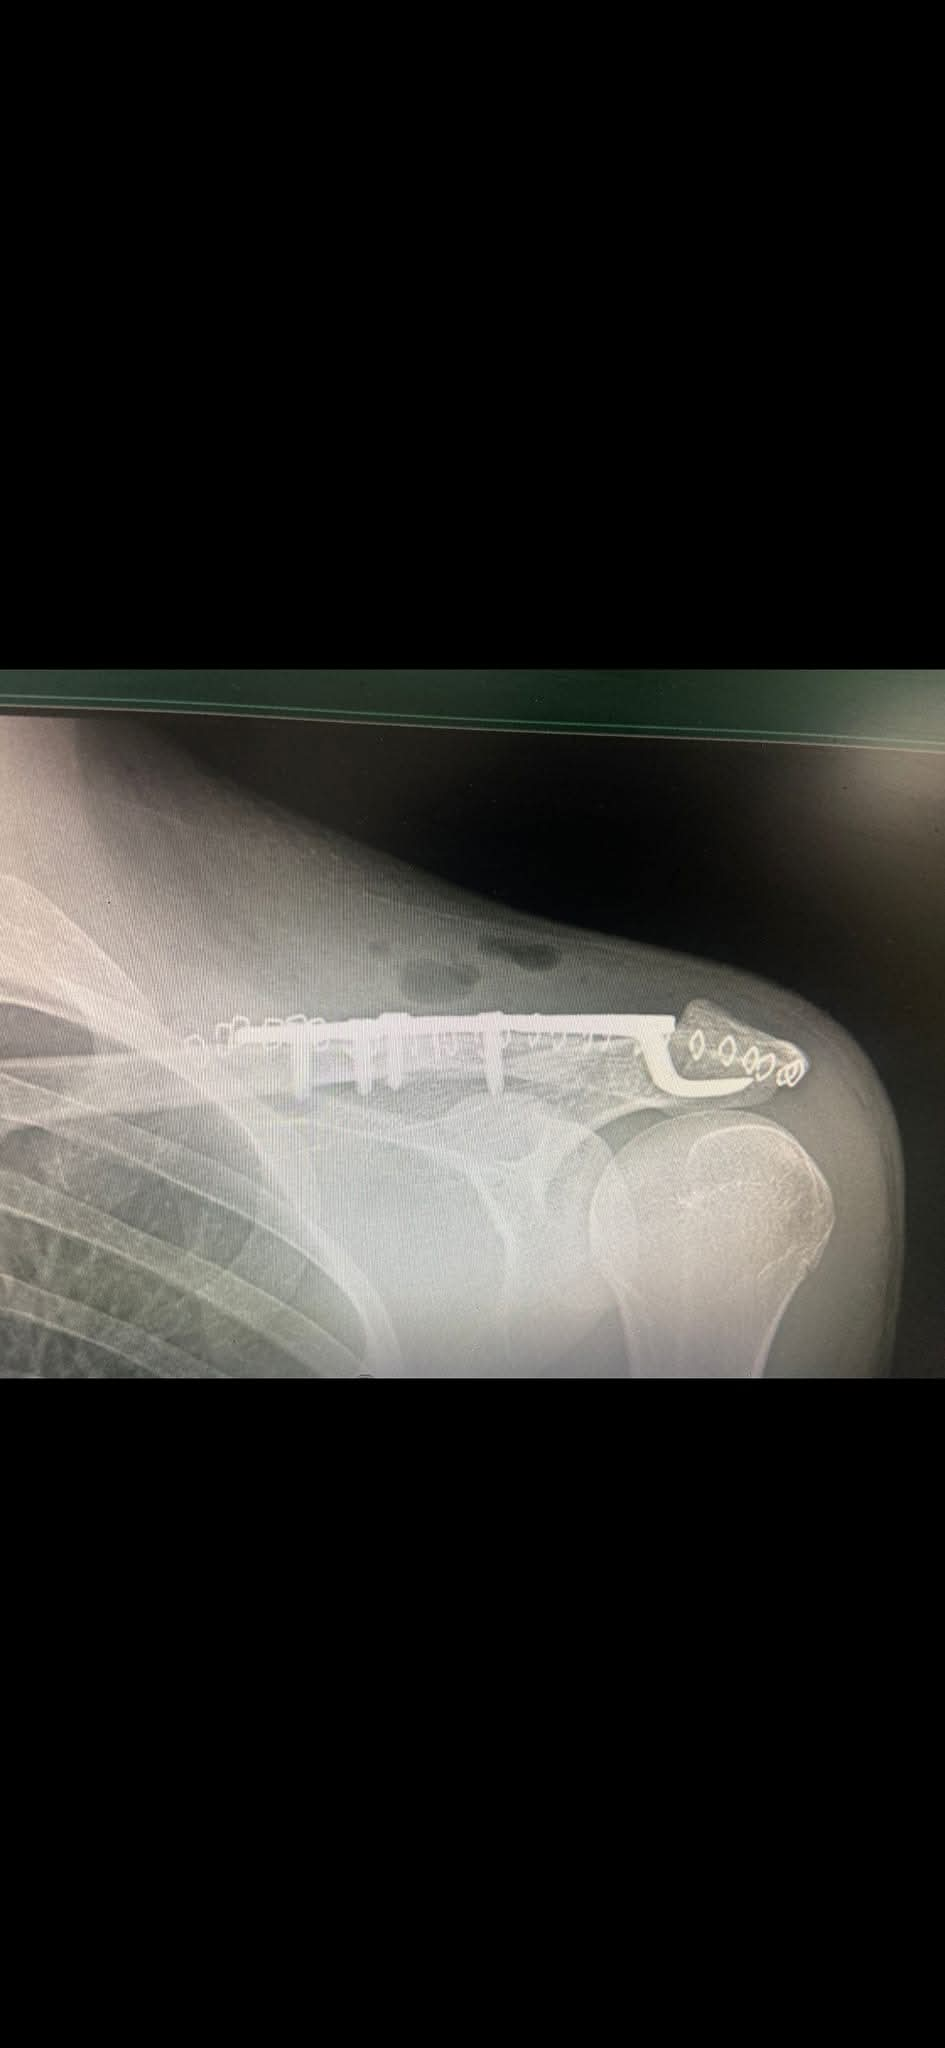

وطنا اليوم -  يقوم بعمليات تثبيت الكسور المعقدة بشكل طاريء وتبديل المفاصل بشكل مبرمج  مما خفف على المواطنين البحث عن أسرة في مستشفيات مركزية رغم صعوبة عمليات العظام من الناحية التقنية في المستشفيات النائية  إضافة الى  استقبال اعداد كبيرة بالعيادات ومعالجة جميع المرضى بالطرق المثلى انه الدكتور الانسان البارع والمتميز يزيد البريزات طبيب العظام في مستشفى الاميرة سلمى / ذيبان عيادة العظام  علماً بأنه كان  مستشفى تحويلي منذ تاسيسه والدكتور البربزات وقبل اربع سنوات في عام 2020  منذ انتقاله للمستشفى يقوم بهذه العمليات ومن بينها  عمليات نوعية لمرضى يعانون من كسور معقدة في الترقوة واجراء عمليات دقيقة ومعقدة لكسور لمرضى في مختلف أنحاء الجسم وعمليات تثبيت الكسور المعقدة وتركيب المفاصل وغيرها الكثير  والديسك " وآلامه وتبعاته وعلاجه وإجراء عمليات معقده وصعبه.

وأجرى الدكتور البريزات عمليات كبرى في جراحة العظام والتي تحتاج إلى مراكز متقدمة ومتطورة. وكذلك العمل على تثبيت أغلب انواع الكسور بطريقة طارئة وتبديل المفاصل بطريقة مبرمجة بما يتناسب مع امكانات المستشفى والتي هي  جزء من  العمليات الدورية بمستشفى الاميرة سلمى في ذيبان  والتي تخفف العبئ على المستشفيات المركزية وعلى المواطن في آن واحد.

وعبر كثير من  المرضى وذويهم عن عظيم شكر هم وامتنانهم للدكتور البريزات على ما بذله ويبذله  من جهود كبيرة واستثنائية في تعامله مع المرضى والمراجعين  ومتابعته الحثيثة لهم والاطمئنان عليهم والتي تكللت جميعها بالنجاح وله الدور الكبير   برفع كفاءة قسم العظام  بالمستشفى بشكل عام والذي  أصبح  متطوراً بالقيام بالعمليات مثل تثبيت الكسور المعقدة و تركيب المفاصل و غيرها.